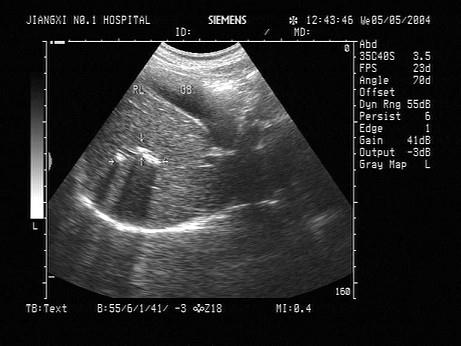

问题 患者体检超声见右肝一点状的强回声光斑,不伴声影,不沿肝管走行,如图所示,考虑为?(?)

选项 A.肝脓肿 B.肝结核 C.肝管结石 D.钙化灶 E.肝内胆管积气

答案 D